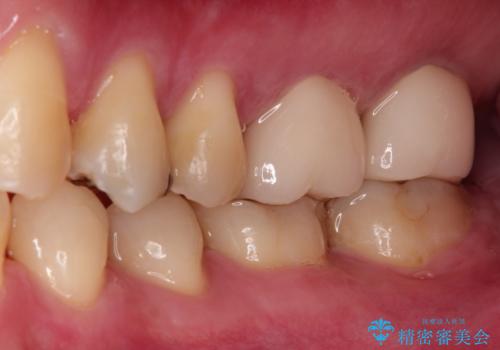

目立つ金歯を自然な色のオールセラミックへ

これらの歯にオールセラミッククラウンを装着することとなりました。

総合治療が可能な当院ならば、矯正後のセラミックの装着がスムーズに行うことが可能です。